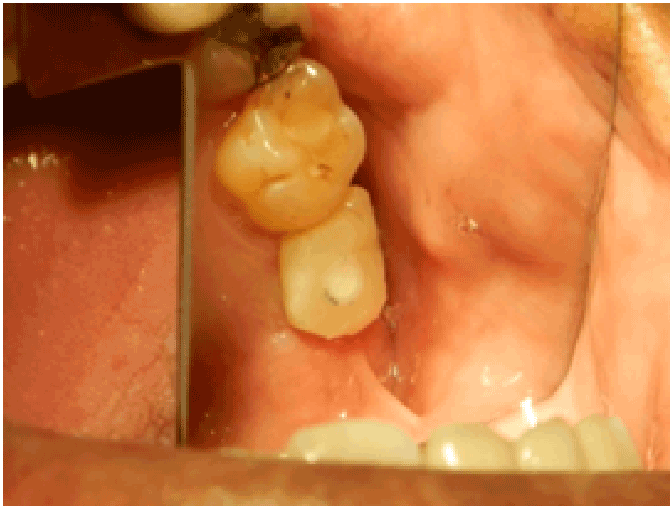

图9:术后3个月暴露左侧埋置假体。测量RFA,放置愈合基台1个月后取印模